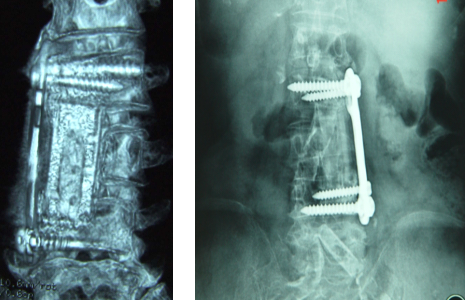

● 椎体间融合及椎体切除后缺损的修复